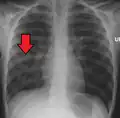

Right middle lobe pneumonia in a child as seen on plain X-ray

X-ray presentations of pneumonia may be classified as lobar pneumonia, bronchopneumonia, lobular pneumonia, and interstitial pneumonia.[75] Bacterial, community-acquired pneumonia classically show lung consolidation of one lung segmental lobe, which is known as lobar pneumonia.[42] However, findings may vary, and other patterns are common in other types of pneumonia.[42] Aspiration pneumonia may present with bilateral opacities primarily in the bases of the lungs and on the right side.[42] Radiographs of viral pneumonia may appear normal, appear hyper-inflated, have bilateral patchy areas, or present similar to bacterial pneumonia with lobar consolidation.[42] Radiologic findings may not be present in the early stages of the disease, especially in the presence of dehydration, or may be difficult to interpret in the obese or those with a history of lung disease.[24] Complications such as pleural effusion may also be found on chest radiographs. Laterolateral chest radiographs can increase the diagnostic accuracy of lung consolidation and pleural effusion.[41]